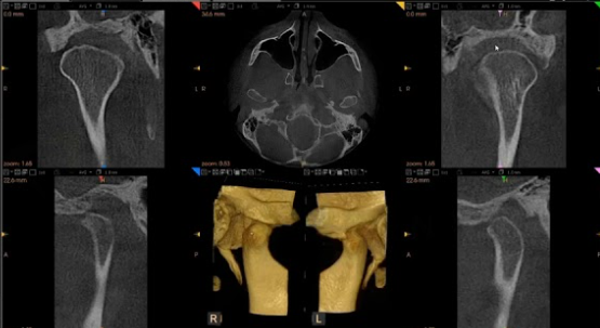

TMJs CBCT

Rt and Left TMJ images